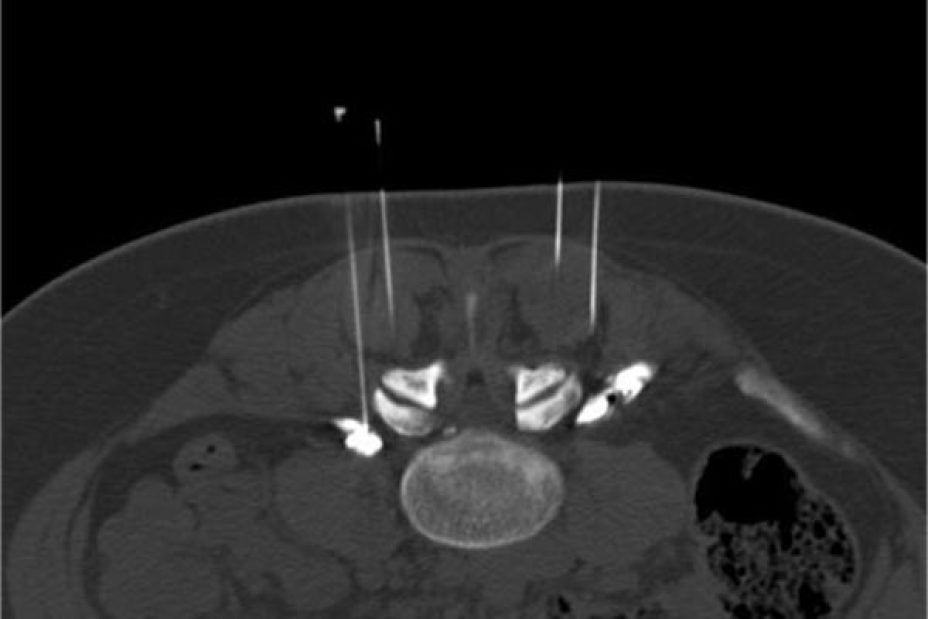

Bei der CT-gesteuerten Schmerztherapie handelt es sich um ein besonders präzises Verfahren. So werden per computertomographischer Planung in Bauchlage des Patienten feine Nadeln millimetergenau an die schmerzenden Strukturen wie Wirbelgelenke oder Nervenwurzeln sowie ggf. auch an einen Bandscheibenvorfall herangeführt. Nach Kontrolle der Nadellage werden z.B. die Wirbelgelenke infiltriert oder aber ein Nervenwurzel mit betäubenden und entzündungshemmenden Medikamenten umspritzt.

Die Behandlung wird grundsätzlich in örtlicher Betäubung mit sehr feinen Nadeln vorgenommen. Der Patient liegt auf dem Bauch auf dem CT-Tisch. Zur genauen Höhenlokalisation der Schmerzstelle wird auf den Rücken ein Metallstreifen /Büroklammer geklebt. Ein so genanntes Topogramm, also eine Übersichtsaufnahme des entsprechenden Wirbelsäulenabschnittes wird angefertigt. Jetzt kann auf dem computertomographischen Schnittbild die Schmerzstelle lokalisiert werden. Auf dem Bearbeitungsmonitor können dann der exakte Eintrittspunkt der Nadel, der Winkel und die Tiefe, sowie die Stelle. in der gespritzt werden soll, ermittelt werden. All diese Parameter werden anschließend mit einem Laserpunkt auf dem Patienten dargestellt. Gefolgt von einer örtlichen Punktion nach steriler Säuberung der Haut kann die feine Punktionsnadel, die eine millimetergenaue Skalierung aufweist, am Schmerzpunkt platziert werden. Es folgt die CT- Kontrollaufnahme zur Dokumentation der exakten Nadellage. Um das Verteilungsmuster des zur verabreichenden Medikamente feststellen zu können, wird eine kleine Menge von verdünntem Kontrastmittel gespritzt. Dann werden Medikamente um die Nervenwurzeln verabreicht (PRT= Periradikuläre Schmerztherapie).